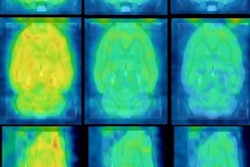

In this study, PiB-PET was performed postmortem on 15 subjects (median age, 33 years) with moderate to severe traumatic brain injury and 11 healthy controls (median age, 35 years) with no symptoms, signs, or diagnoses of neurological disease or abnormalities as shown on a brain MRI. The healthy participants also had a normal score on a mental exam.

The researchers also measured the PiB distribution volume ratio and standardized uptake value (SUV) ratio in the PET images, specifically looking at cortical gray matter, white matter, and multiple cortical and white-matter regions of interest, as well as striatal and thalamic regions of interest. Those regions of the brain are associated with executive function and memory and are likely to show early signs of Alzheimer's disease.

The analysis found that subjects with traumatic brain injury showed significantly greater PiB distribution volume ratios in cortical gray matter and in the striatum, but not in the thalamus or white matter, compared with the control group.

Increases in PiB distribution volume ratios in patients with traumatic brain injury were also seen across most cortical subregions and were replicated in SUV ratios. Control subjects, meanwhile, showed relatively low PiB binding, predominantly in the central white-matter and deep gray-matter structures.